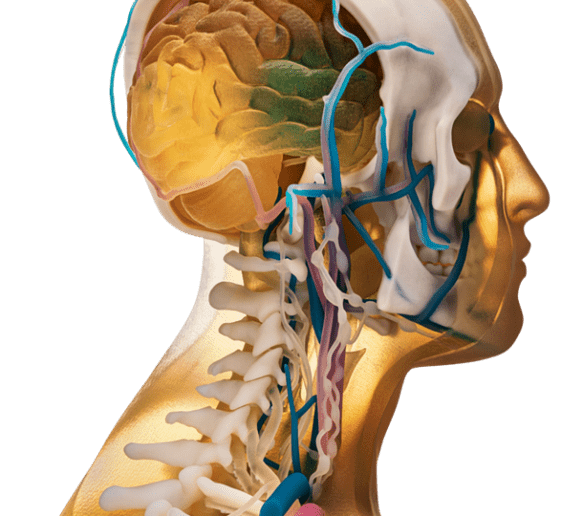

A kutatás a feji és nyaki régió kisebb méretű anatómiáinak 3D nyomtatott fantomjainak gyártásával kezdődik, majd fokozatosan egyre nagyobb és összetettebb anatómiák előállítását célozza meg – egészen az első fázis végpontjáig, a szívmodell és egy teljes emberi törzs 3D nyomtatásáig, teljes röntgenfelvételi pontossággal.